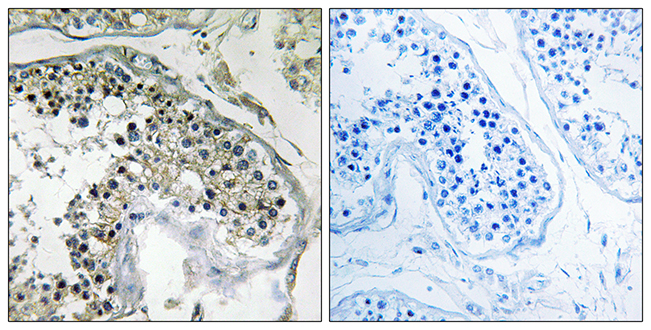

ApplicationsImmunoHistoChemistry

ReactivityHuman

- SizePrice